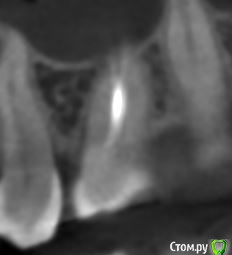

krokomot Опубликовано 19 февраля, 2020 Поделиться Опубликовано 19 февраля, 2020 в медиальном корне недопломбировка и наличие вероятно 4ого канала. Ссылка на комментарий

dmitrib81 Опубликовано 20 февраля, 2020 Автор Поделиться Опубликовано 20 февраля, 2020 Зуб делали много лет назад. Примерно неделю назад появились периодические боли, бывает целый день не болит, потом снова ноющая боль. С приёмом пищи никак не связано. На горячие и холод реакции нетПодскажите, может ещё прислать фоток из КТ Пикассо, а то я в этом ничего не понимаю, просто разных фото экрана прислал, без какого-либо понимания, на что смотреть.. Ссылка на комментарий